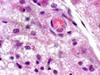

what is pictured

a macrophage in the center of the image